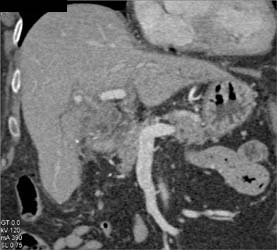

Fibrolamellar Hepatoma With Neovascularity